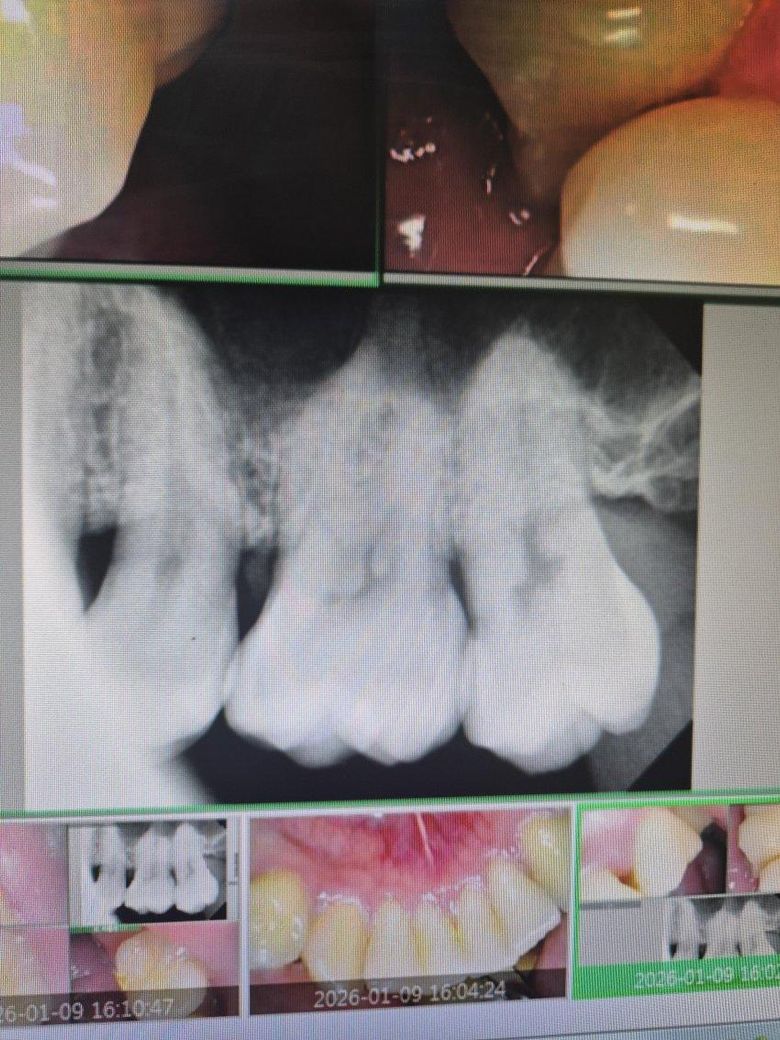

안녕하세요 어제 인접면충치질문햇던사람입니다

많은분들께서 인접면초기라 굳이 갈아낼필요는없다고 하셧습니다

근데지금 이가 처음시린지는6일쨰 치과에 간지는 3일째가 되엇습니다

현재 침대에 좀오래누워있으면 맨왼쪽어금니가 묵직하고 잇몸사이로 찬물을 왓다갓다하면 시린건 비슷합니다

오늘좀 질긴? 닭강정을 일부러 그쪽으로 씹어봣더니 미약한 통증도있는거같습니다

혹시 이게 치아가 민감해져서 그럴수가있나요? 그리고 3일전에 치과에서 시린이약? 마우스피스에 잴같은거 뿌린후

뭔 기계에 연결해서 몇분간 물고있엇습니다 혹시 이게 효과를보려면 몇번더해야하는건가요??

다음치과는 2주뒤라 여러분들께 여쭤보고싶습니다

• 1번 째 사진

충치가 커보이지 않더라도 씹을때 통증, 시린증상이 지속되면 치료를 하는게 좋을 것 같습니다

단순 치아민감으로 시린거라면 시린이처치하면 바로 괜찮아집니다